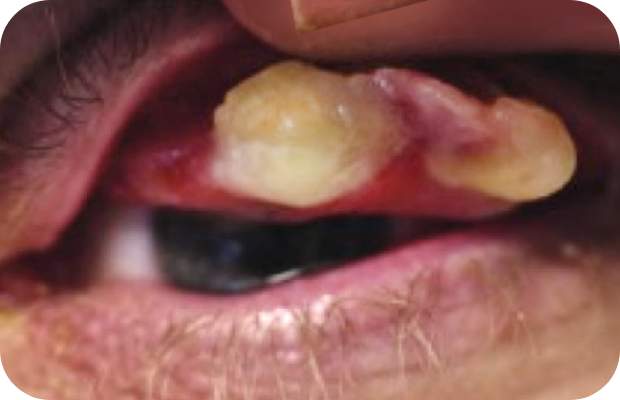

PLGD-1 lesion image gallery

Images of ligneous lesions in real patients with PLGD-1

2. Sadasivan A, Ramesh R, Mathew DG. Ligneous periodontitis in a patient with type 1 plasminogen deficiency: a case report and review of the literature. Case Rep Dent. 2020;2020:5680535.